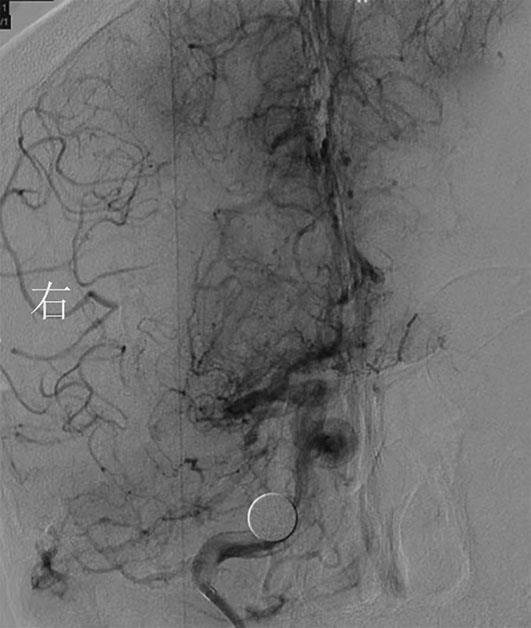

• 全身抗凝联合血管内治疗颅内静脉窦血栓形成的临床效果观察

2022, 47(7):784-789. DOI: 10.13406/j.cnki.cyxb.003064

摘要:目的 对全身抗凝联合血管内治疗在颅内静脉窦血栓形成(cerebral venous sinus thrombosis,CVST)中的临床治疗效果进行观察评估。方法 回顾性纳入2008年6月至2021年8月于海军军医大学第一附属医院接受治疗的CVST患者,根据治疗方式不同分为抗凝治疗(anticoagulation treatment,AT)组和血管内治疗(endovascular treatment,EVT)组,分析2组患者的临床资料及治疗效果。结果 共纳入54例患者,其中AT组27例,EVT组27例。EVT组血栓累及上矢状窦和直窦的患者比例、累及静脉窦数量、入院改良Rankin量表(modified Rankin scale,mRS)评分明显高于AT组(P<0.05)。治疗后2组患者凝血酶原时间、活化部分凝血酶时间较治疗前均明显延长,AT组D-二聚体水平较治疗前明显下降(P<0.05)。EVT组治疗后血管再通率明显高于AT组(P<0.05),总住院时间、重症监护室入住时间、并发症发生率、生存情况以及神经功能预后均与AT组无统计学差异(P>0.05)。2组患者治疗后mRS评分均较治疗前明显下降(P<0.05)。结论 对于血栓累及广泛、全身抗凝疗效不佳的重症CVST患者,在标准抗凝的基础上联合血管内治疗可作为一种安全有效的潜在治疗方案。